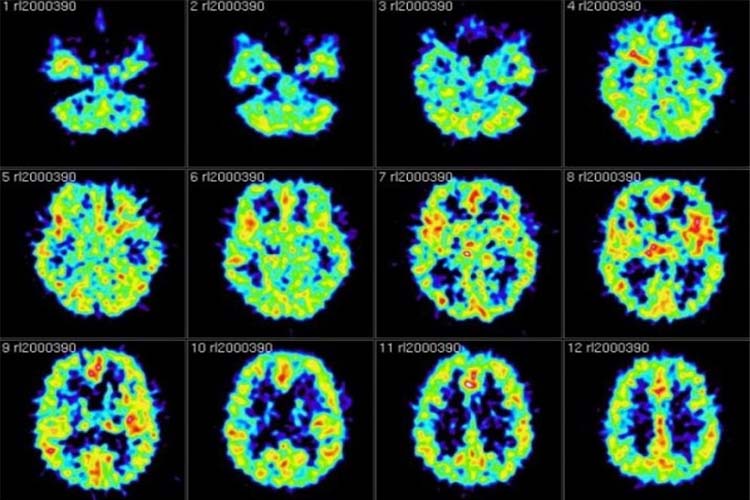

گروهی از محققان کالج دارتموث و دانشگاه پرینستون با استفاده از روش تصویرسازی رزونانسی مغناطیسی کارکردی (fMRI) اسکن مغزی یک گروه ۲۵ نفرهی حاضر در یک آزمایش حافظه، تهیه کردند.

پس از مطالعهی لیست کلمات آمیخته با تصاویر به نمایش در آمده، از شرکت کنندگان خواسته شد تا کلماتی را که مطالعه کرده بودند فراموش کنند یا بخاطر بیاورند. زمانی که از آنها خواسته شد تا کلمات موجود در لیست را فراموش کنند، اسکن fMRI نشان داد که فعالیت مغز مرتبط با کلماتی که به همراه تصاویر به نمایش درآمده، مطالعه شده بودند، از بین رفتند.

هنگامی که از شرکت کنندگان خواسته شده تاکلمات موجود در آن لیست را بخاطر بیاورند، فرآیند از بین رفتن افکار مرتبط با تصاویر، در اسکن fMRI مشاهده نشد. اما زمانی که از آنها خواسته شد تا کلمات را فراموش کنند، گستردگی افکار از بین رفته، نشان میداد که شرکت کنندگان تا چه حد کلمات مطالعه شده را بخاطر میآورند.

نوع رانش آرام افکار هر یک از شرکت کنندگان متفاوت و منحصربفرد است. ما در پژوهش خود، بر سطح فعالیتهای بصری و تصویری به عنوان شاخصی از تغییرات زمینهای تمرکز داشتیم چرا که ما بصورت هدفمند فعالیتهای تصویری را به ذهن شرکت کنندگان وارد کردیم ... و ما ابزارهای حساس و دقیقی برای سنجش فعالیتهای تصویری با fMRI در اختیار داشتیم.